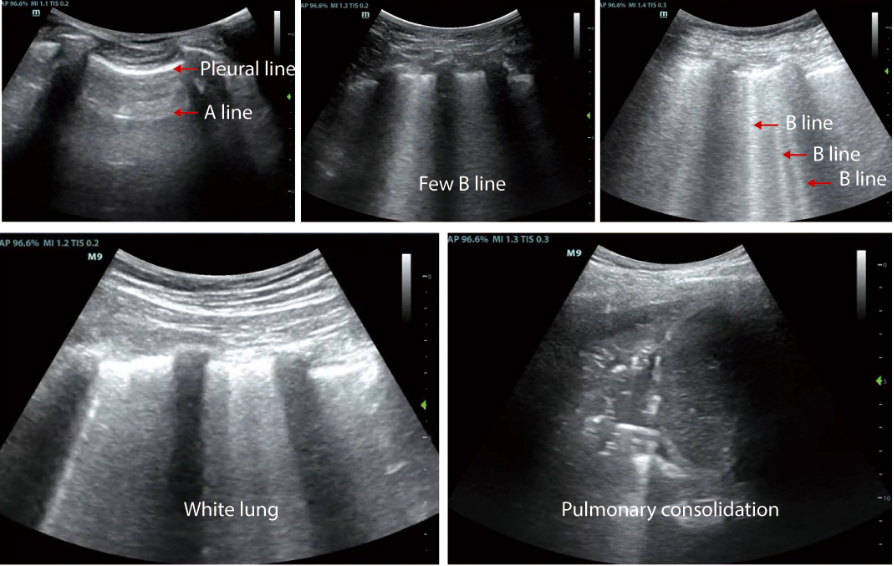

- 1. Professional lung examination mode to observe changes in lung conditions